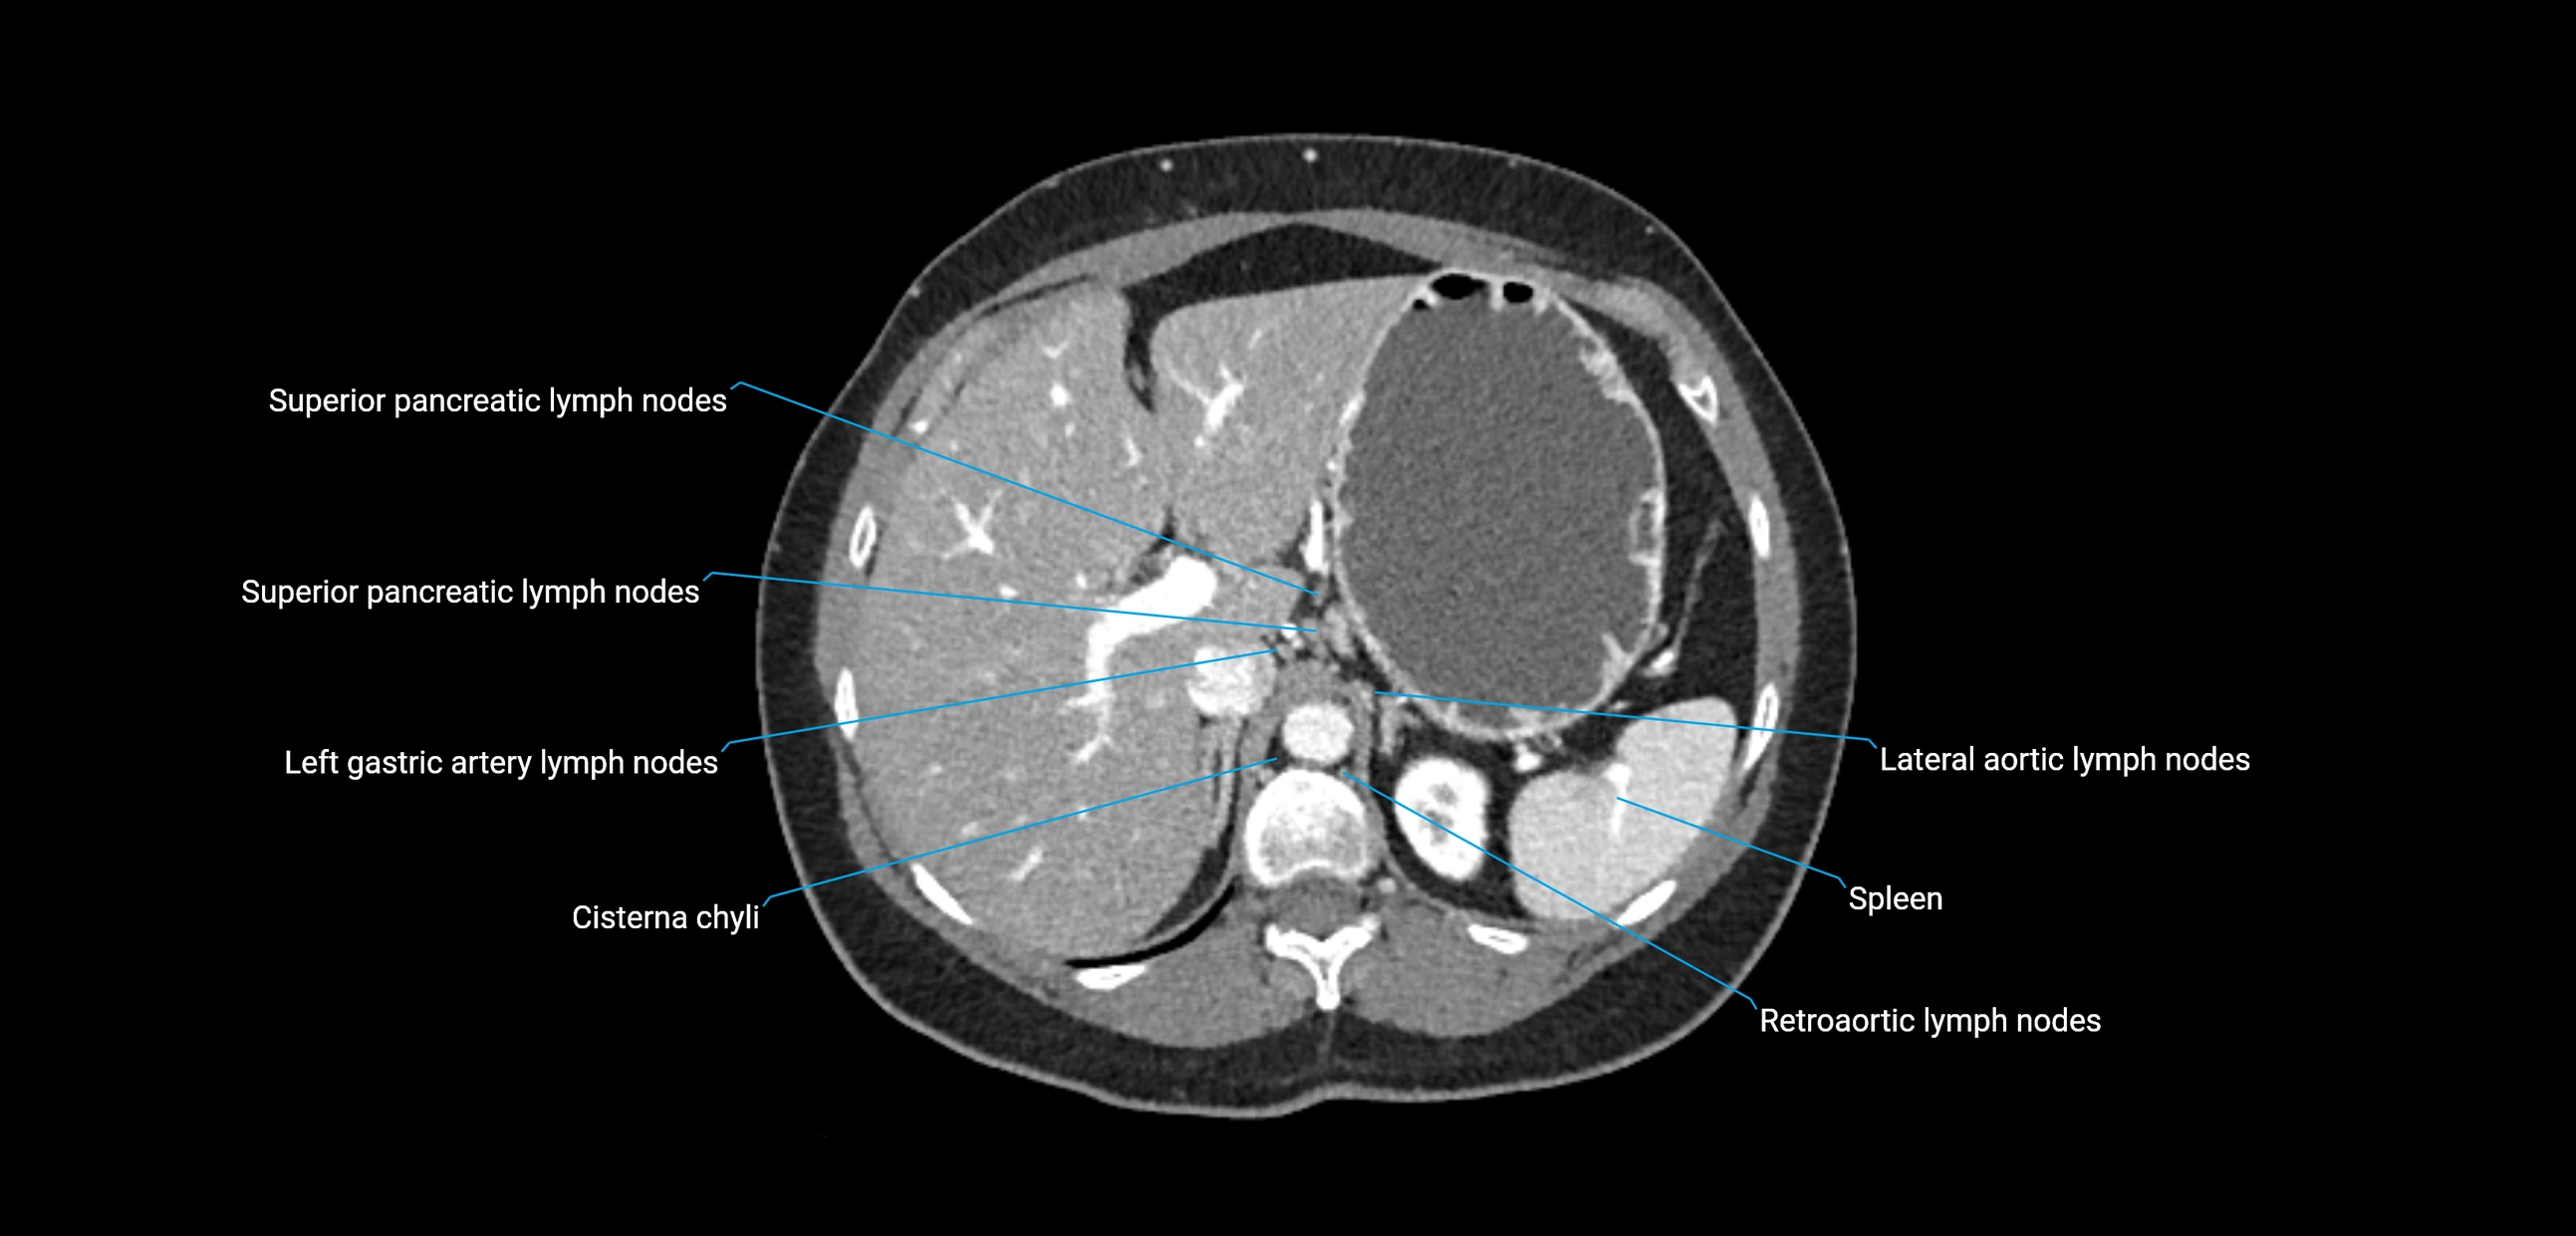

MRI images

image